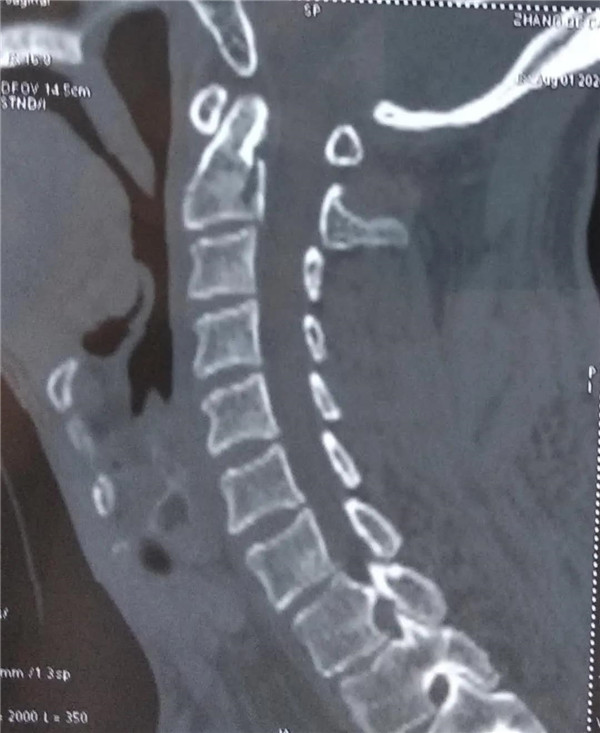

该病人因从高处坠落至颈部疼痛,活动受限。伤后就近在乐平市一家医院治疗,行CT和磁共振检查,显示颈2椎体齿状突骨折,随时有危及生命或四肢瘫痪风险,医院建议立即转南昌大医院手术治疗,因患者为景德镇鱼山人,想回景德镇市治疗,经多方打听,了解到市二医院能做这种手术,遂转入市二医院骨一科治疗。

由于患者上颈椎高度不稳定,患者随时可能有瘫痪、危及生命的风险,入院后科室高度重视,立即组织术前病情讨论,制定手术方案,经颈椎三维CT检查颈1、2椎体无明显变异,颈1椎弓根直径约4mm,刚好可以打入一枚3.5mm椎弓根螺钉,术中不能有丝毫的偏差,否则会造成患者术中大出血,瘫痪甚至危及生命。由吕志华副院长、王小明主任、罗明华副主任医师、杨华主治医师组成的手术团队,在麻醉科、手术室大力配合下,顺利完成手术,整个过程用时90分钟,出血约100毫升。术后患者顺利返回病房,第二天就可坐起。